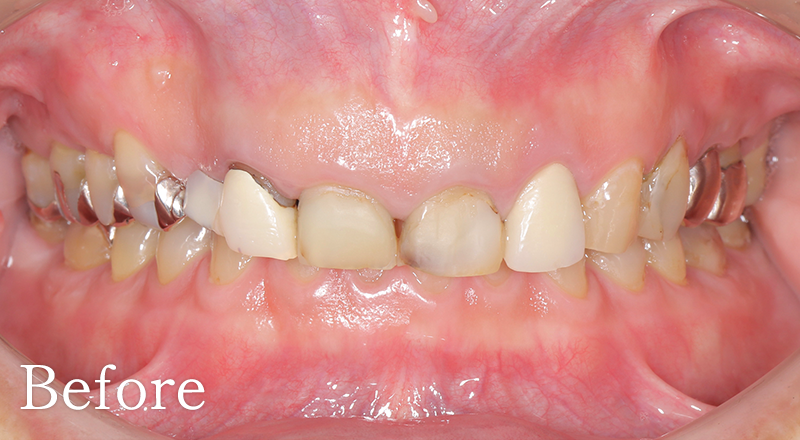

CASE2

骨格2級患者に対し、審美と機能の両立を図り治療を行なった1症例

主訴 右上のブリッジがよく外れる

治療内容 上犬歯インプラント、GBR、咬合再構成、上顎前歯部歯冠長延長術、セラミック治療

治療期間 約2年

費用 診断料:22万円(税込)

右上犬歯インプラント埋入手術:27.5万円(税込)

GBR:11万円(税込)

セラミック補綴:22万円(税込)

セラミック治療:11万円(税込)×18本